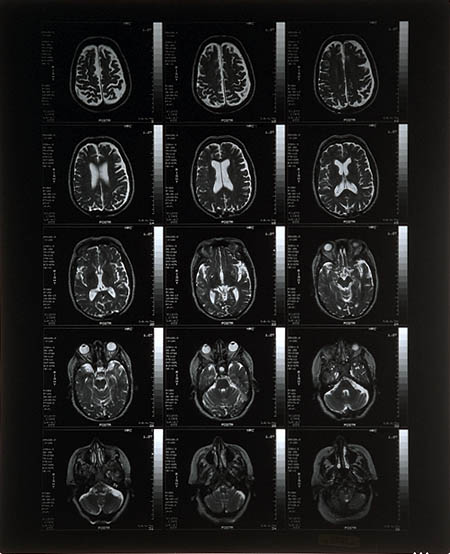

Streszczenie: Agenci szukają mordercy, który potrzebując hormonów ludzkiej przysadki zabiera je swoim ofiarom.